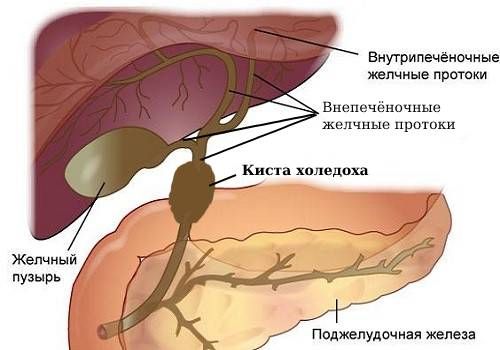

Фотографии и изображения, связанные с симптомами первичного склерозирующего холангита